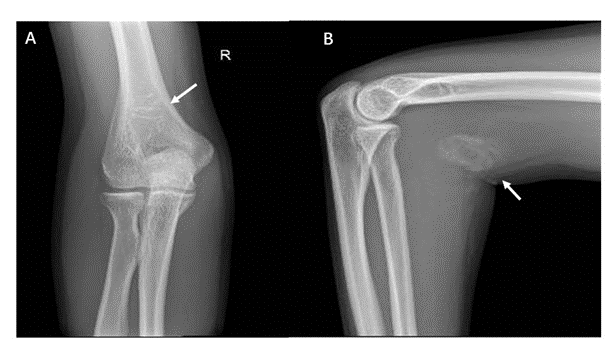

Ultrasonography is the best investigation modality in differentiating between cystic and solid lesions, and for early diagnosis of heterotopic bone formation. Ultrasonography in our case demonstrated a heterogeneous solid mass and some internal blood flow on the Doppler examination. It was noticed the hyperechoic rim surrounded by a hypoechoic rim and the central area that is hypoechoic as well (Figure 2). The calcified lesion was located over distal humerus just above the olecranon fossa on AP radiograph. The calcifications typically become more peripherally oriented and coarse in appearance with a calcified peripheral rim with a lucent center, the calcifications appear as amorphous and flocculent simulating osteoid matrix in brachial muscles (Figure 3).

Figure 3: The typical radiographic appearance of MO is circumferential calcification with a lucent center and a radiolucent cleft (“popcorn sign”) that separates the lesion from the cortex of the adjacent bone. This pattern of peripheral predominate calcification is a clinically significant feature which distinguishes this entity from (parosteal osteosarcoma) that tends to contain centrally located calcifications. The calcified lesion is located over distal humerus just above the olecranon fossa on AP radiograph (an arrow in A). The calcifications typically become more peripherally oriented and coarse in appearance with a calcified peripheral rim and a lucent center (A). The calcifications appear as amorphous and flocculent simulating osteoid matrix in brachial muscles (an arrow in B)